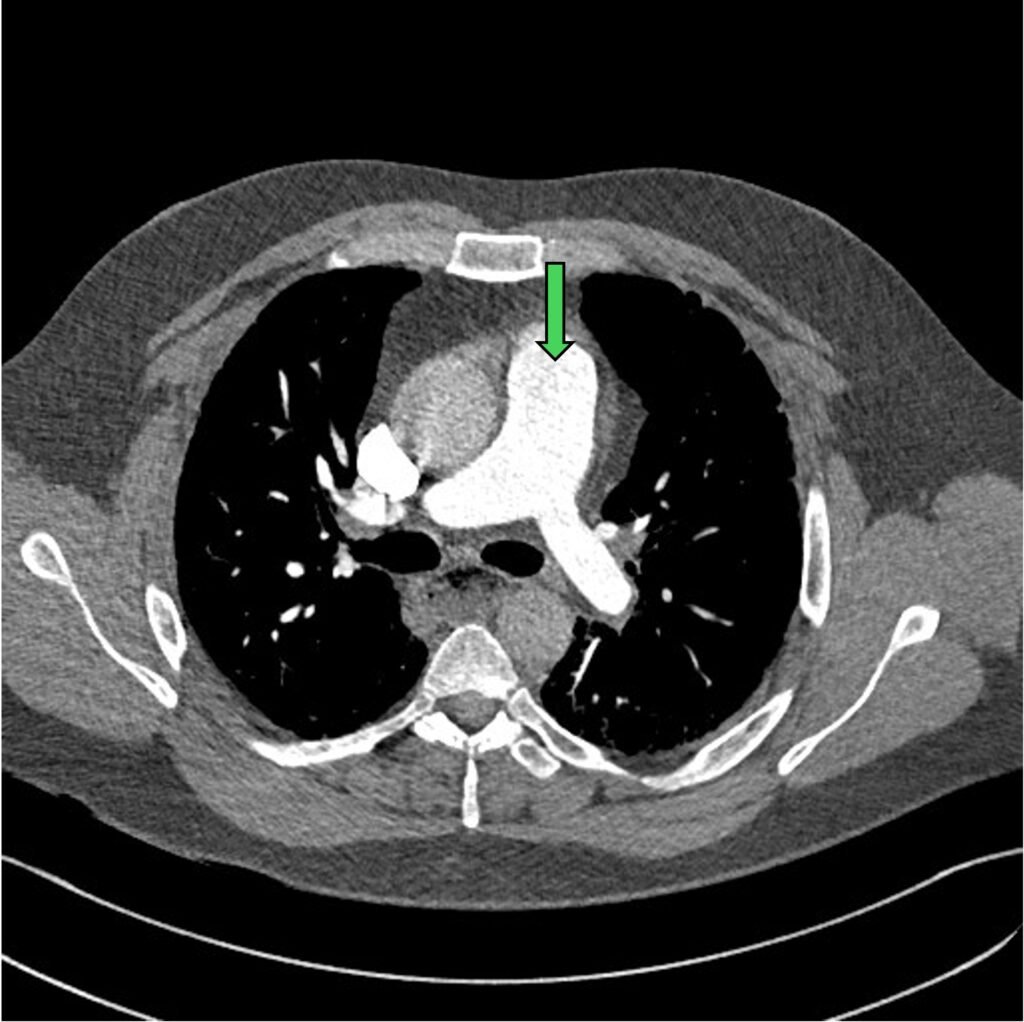

The normal CTPA has continuous flow of hyper-attenuated contrast within the vasculature of pulmonary artery (PA) and its branches.

Figure 2: CTPA with contrast within the bifurcation of the main PA